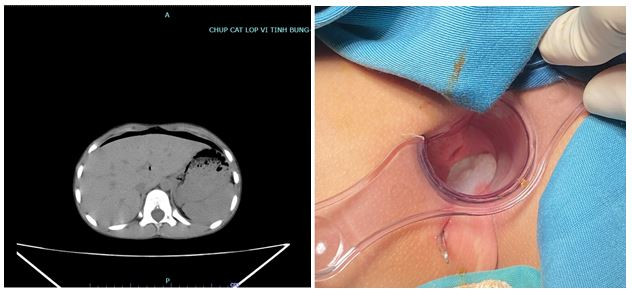

| Hình ảnh khí tự do ổ bụng qua phim chụp CT và vết thương trực tràng của người bệnh |

Em T được đưa vào Bệnh viện đa khoa tỉnh Phú Thọ sau tai nạn 6h trong tình trạng đau tại vết thương vùng tầng sinh môn, đau bụng vùng hạ vị, tỉnh táo, huyết động ổn định.

Qua thăm khám, các bác sĩ kết luận chiếc bút đâm vào tầng sinh môn xuyên thủng trực tràng vào trong ổ bụng gây viêm phúc mạc. Khả năng còn các tổn thương cơ quan khác trong ổ bụng